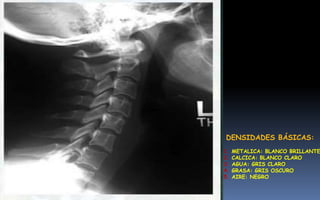

Distribución en el cuerpo de las

densidades radiológicas que se

consideran básicas: aire (gas),

agua, grasa, calcio (ósea) y

densidad metálica, determinan

lo que se distingue en la

radiografías normales.

DENSIDADES BÁSICAS:

1. METALICA: BLANCO BRILLANTE

2. CALCICA: BLANCO CLARO

3. AGUA: GRIS CLARO

4. GRASA: GRIS OSCURO

5. AIRE: NEGRO